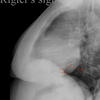

Rigler's sign

to assess LV size

Date: 04/28/2014

Views: 4821